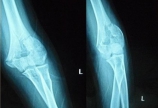

患者杨某,女,18岁,因摔伤致左肘部疼痛、肿胀活动不利2小时,急诊以“左肱骨髁间粉碎性骨折”收入院。